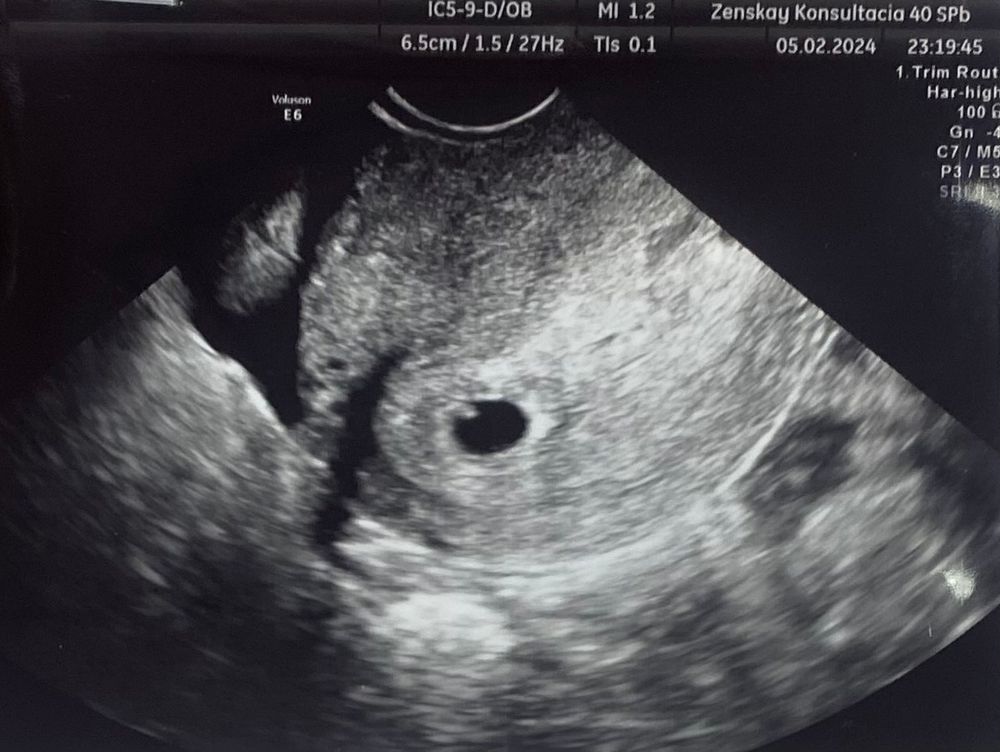

Узи в 6 недель!!

Была я значит на узи. И мне написали в заключение пя 9 мм, эмбрион. Ж/мешок четко не видно. Это вообще нормально ? И такое может быть ?

Переделайте УЗИ позже. Анэмбрионию ставят, если ЖМ нет при ПЯ 20 мм, или нет эмбриона при ПЯ 25 мм.

Mura, без ЖМ эмбриона быть не может. Вам написали КТР эмбриона? Может перепутали или просто не написали, сделайте УЗИ позже в другом месте

Там в пя действительно что-то есть, и это не похоже на жм. Может эмбрион закрыл жм ?

Mura, при таком размере не понятно, очень мелко. Может быть эмбрион и ЖМ там вместе, к следующему УЗИ думаю все станет понятно

я бы переделала узи в другом месте,сначала появляется жм всегда,потом уже эмбрион

Ну по идее это ни есть хорошо. Если нет желточного мешочка, эмбриону не откуда брать питательные вещества. Обычно сначала дм появляется, потом эмбрион. Впервые такое слышу.